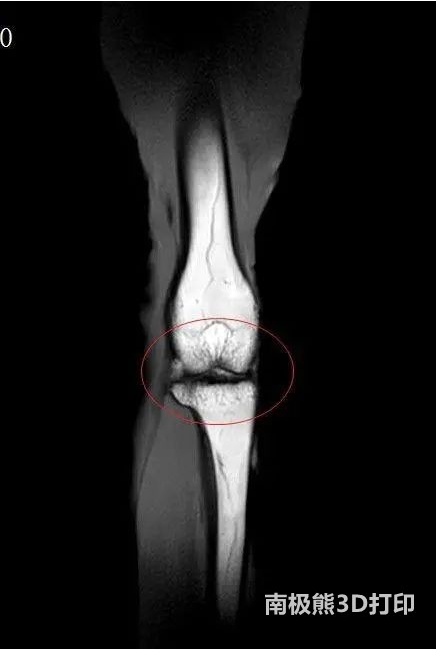

老年人膝蓋疼、走路難?關(guān)節(jié)軟骨老化有望用3D打印技術(shù)恢復(fù)如初

D打印骨軟骨支架修復(fù)老年關(guān)節(jié)軟骨損傷的論文近日在《Biofabrication(生物制造)》上發(fā)表,此項(xiàng)目由粵港澳大灣區(qū)科研人員共同研究,使老年人關(guān)節(jié)軟骨磨損、退化有望恢復(fù)如初。